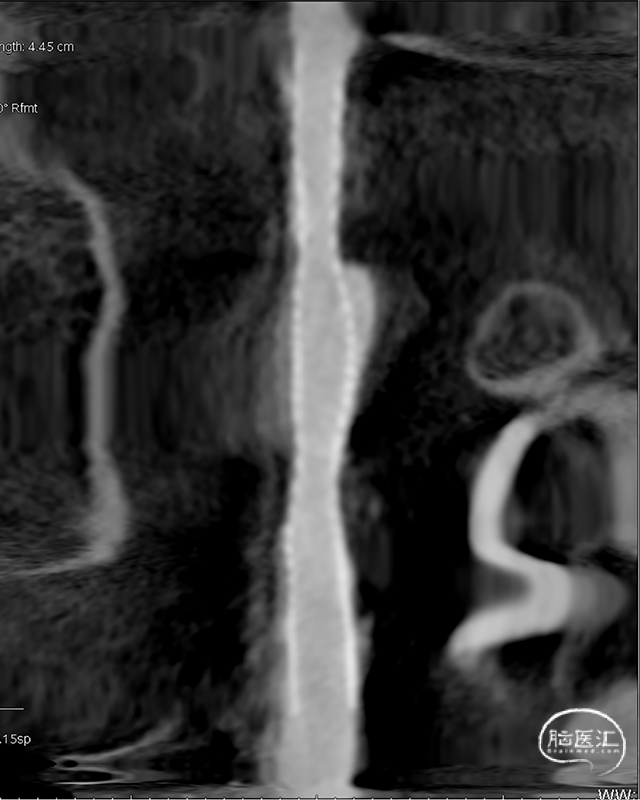

术后即刻DSA。

术后即刻稀释造影:“拉直”可见支架贴壁良好。